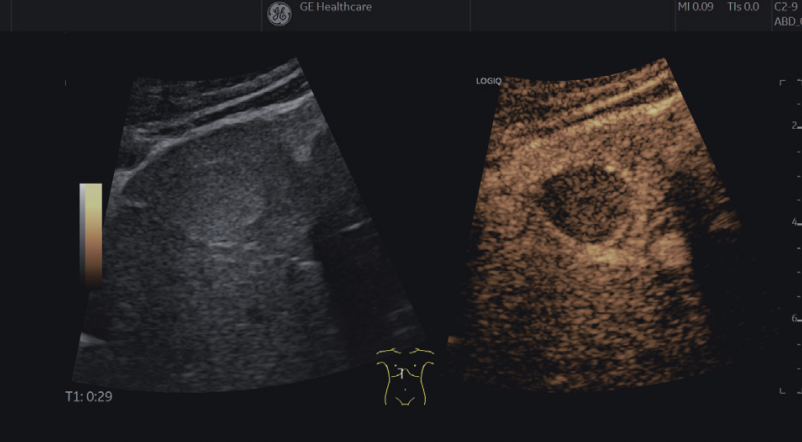

GE超声的造影技术具有高保真调幅造影和脉冲反相谐波造影两种模式。

高保真调幅造影技术属于基波造影,通过精确调整发射脉冲的幅度及相位,实现造影剂信号的完美提取,具有更好的深部敏感性。

脉冲反相谐波造影技术属于谐波造影,具有良好的分辨率,更适合位置较浅的器官部位造影。